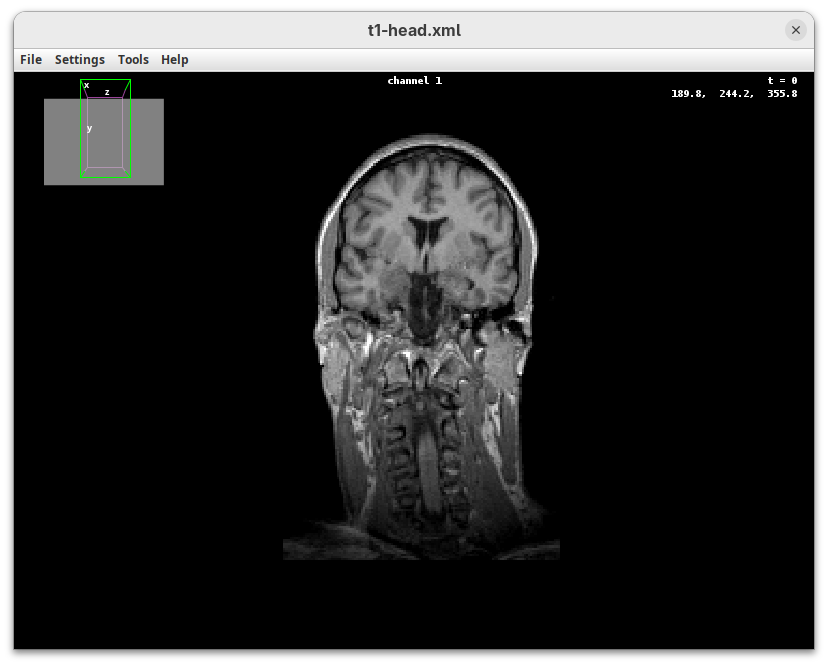

BigDataViewer (Pietzsch et al. 2015) is one of the most important tools for visualizing large, multidimensional datasets. It provides a simple and intuitive interface and shortcuts to swiftly navigate through your sample even on a regular laptop. This is possible because of the underlying file format used by BigDataViewer: the XML/HDF5 combo. Therefore, before opening the plugin, we must convert our dataset.

Plugins>BigDataViewer>Open XML/HDF5and select thet1-head.xml.

The BigDataViewer interface will open showing an optical section of the head sample.

Getting familiar with BigDataViewer is an essential skill for navigating large 3D datasets. It’ll also be important for the multiview registration pipeline. So, take the time to learn the basic commands and shortcuts. It is nicely intuitive. The BigDataViewer’s page on the ImageJ Docs has the official documentation and we can also go to Help > Show Help for an up-to-date overview.

Some of the movements to try:

Left-click and drag: turn the sample around the mouse pointer at any arbitrary angle.Right-click and drag: move the sample in the XY plane (of the view).Scroll: move through the Z plane (of the view). UseShift+Scrollto move fast.Ctrl+Shift+Scroll: zoom in or out.

But, most importantly, are the commands to put your sample back to its original orientation or along any of the original dimension axes:

Shift+Z: orient the sample on the XY plane.Shift+X: orient the sample on the ZY plane.Shift+Y: orient the sample on the ZX plane.

Finally, a visual tip. The default interpolation between image slices is nearest-neighbors. Press I to activate the tri-linear interpolation to obtain a much smoother (and improved) data visualization.